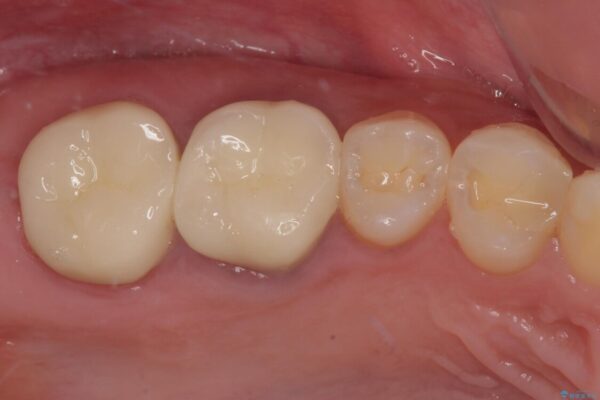

スペースが整った段階で、右下の第一大臼歯と第二大臼歯にインプラントを埋入。

その後、挺出していた右上第一大臼歯と第二大臼歯に装着されていた銀歯についても、審美性と適合性の向上を目的に、オールセラミッククラウンにやり替えました。

これにより、より自然で美しい見た目と、高い精度の咬合が得られています。

治療後

• 挺出歯を圧下してスペースを確保!目立たない部分矯正で下顎大臼歯にインプラント治療を実現 治療後画像